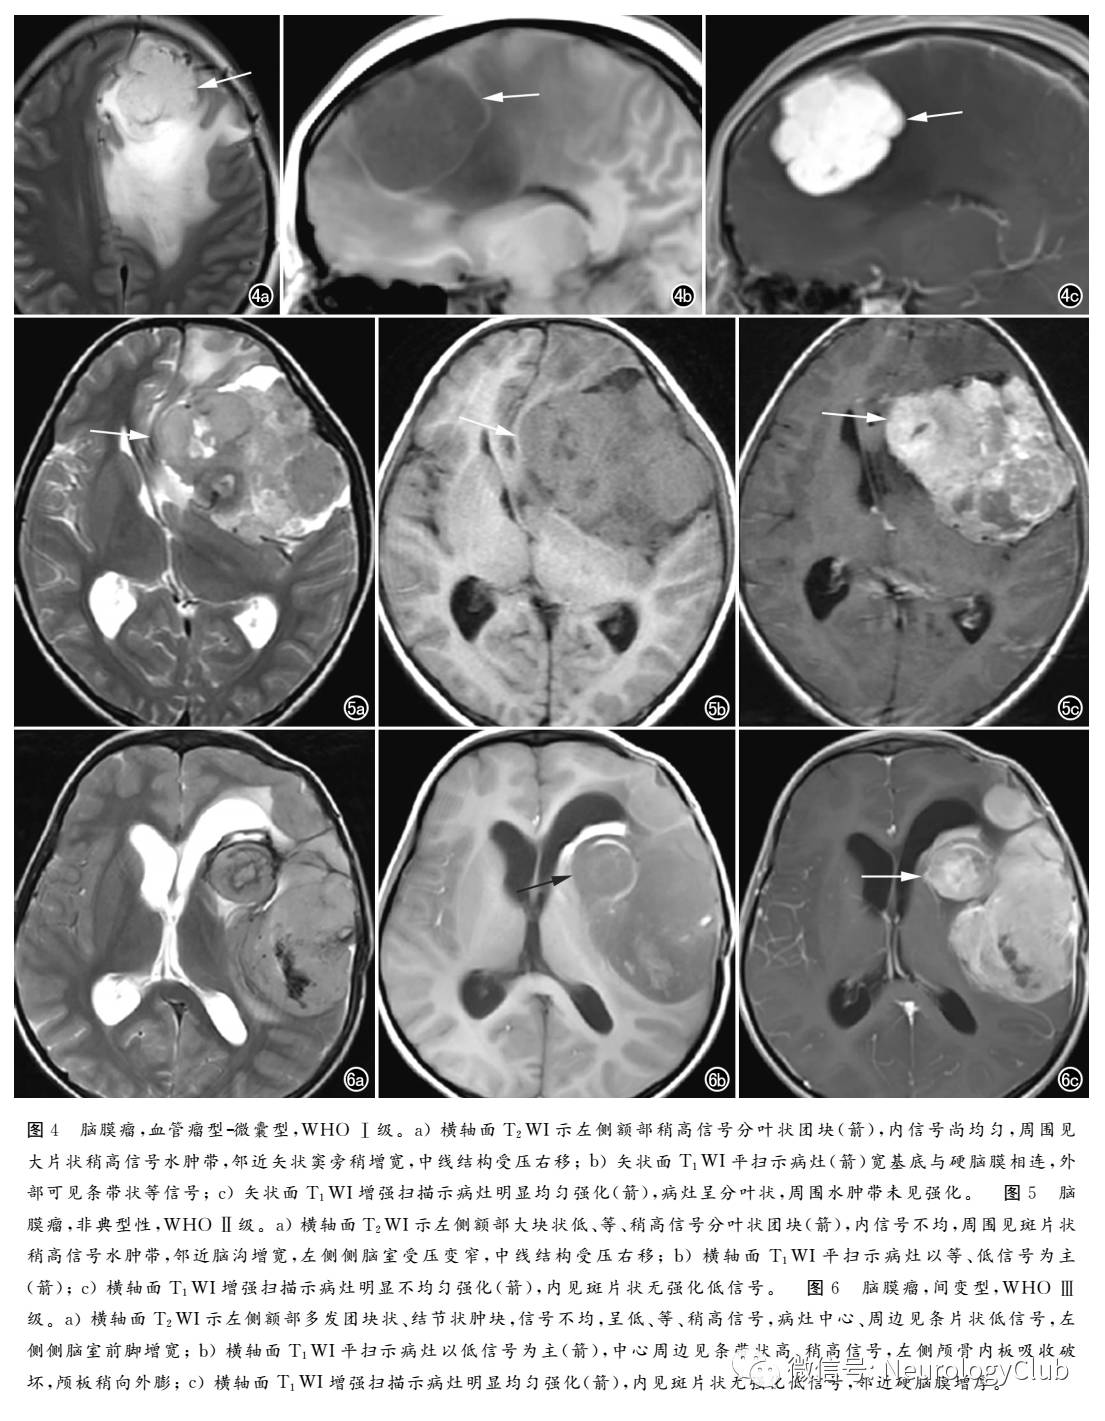

血管瘤型是一种富含血管的脑膜瘤,肿瘤内血管大部分为小血管.血管壁薄,发生透明变性,WHO I级MRI表现为T1WI呈均匀稍低信号,T2WI呈高信号且信号强度较其他亚型脑膜瘤明显增高(图4),可能与丰富的血窦内含有缓慢流动的血液及肿瘤内血管退变后引起水分积聚有关,肿瘤内可见流空的血管信号,增强扫描呈明显强化,肿瘤周围水肿常见,但多为轻度

微囊型又称湿性脑膜瘤或空泡状脑膜瘤,组织学特征为肿瘤细胞突起、相互交织构成大量细胞外腔隙亦即微囊,WHO I级MRI主要表现为类圆形脑外占位性病变,边界多较清楚,邻近脑实质受压移位,多以长T1信号为主,部分区域可见等信号,与脑灰质信号相近该种类型肿瘤主要特点为肿瘤实体呈明显的长T2信号,部分病变信号强度与脑脊液相近(图4)。增强扫描多呈明显强化,其内可见散在点片状低信号及囊状未强化区,瘤周水肿发生率较高

非典型性WHO II级,是II级脑膜瘤中最常见的病理类。非典型性脑膜瘤病理诊断标准为:①4个/10HPF≤有丝分裂指数≤20个/10HPF;②有丝分裂指数<4个/10HPF,具备以下指标中至少3个也可以明确诊断,包括大核浆比例的小细胞、巨核、连续层状生长、细胞过多及灶性地图样坏死MRI图像上可见肿瘤体积较大,以宽基底与脑膜相连,形态不规则、分叶状,边缘毛糙,瘤周水肿,可见白质塌陷征或脑回挤压征,瘤灶信号不均,伴出血、囊变、坏死,钙化少见,增强扫描呈明显不均匀强化,脑膜尾征多粗短、不规则(图5)。肿瘤常缺乏黑环征或白环征,边缘模糊,可见局部颅骨破坏,后者提示肿瘤已侵犯软脑膜或侵蚀颅骨。

间变型病理特点为异型性显著、病理性核分裂像增多、瘤内可有广泛坏死、囊变等,WHO II级。间变型脑膜瘤MRI表现缺乏特异性,瘤体形态不规则或呈分叶状,多以宽基底与硬膜相连,邻近脑膜广泛增厚,脑膜尾征多见。肿瘤内信号不均、较为混杂,多表现为T1WI呈等或稍低信号,T2WI呈高或等信号由于瘤体生长迅速,瘤内常有囊变、出血、坏死及钙化,MRI信号也呈多样性(图6)。